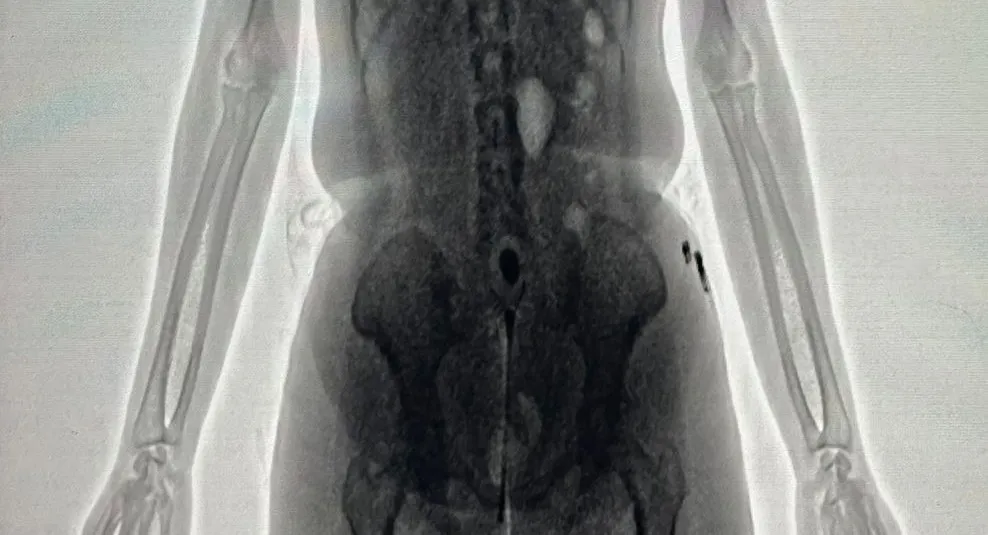

De acordo com a Secretaria de Administração Penitenciária e Ressocialização (Seap), a visitante, companheira de um dos internos, transportava cerca de 20 gramas de uma substância semelhante à maconha escondida nas partes íntimas. A tentativa foi descoberta com o auxílio do equipamento BodyScan, que apontou a presença de um objeto estranho por meio das imagens captadas.

A ocorrência foi informada à Direção do Conjunto Penal, que determinou o arquivamento das imagens do BodyScan para fins administrativos e legais. Em seguida, a visitante foi encaminhada à Delegacia de Polícia de Barreiras, sob escolta da Polícia Militar, seguindo o protocolo adotado para situações dessa natureza.